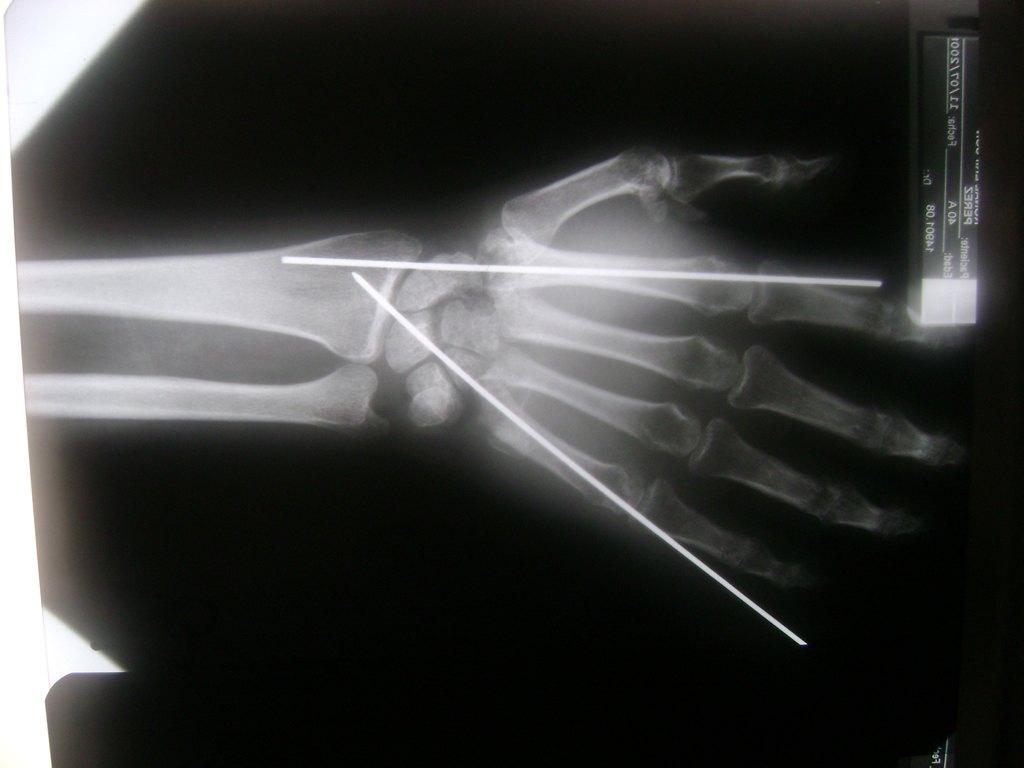

Cirugías de Muñecas

Los procedimientos más comunes en cirugía de la mano son aquellos destinados a reparar traumatismos, incluyendo lesiones de tendones, nervios, vasos sanguíneos, y articulaciones; huesos fracturados; y quemaduras, cortes, y otros daños de la piel.